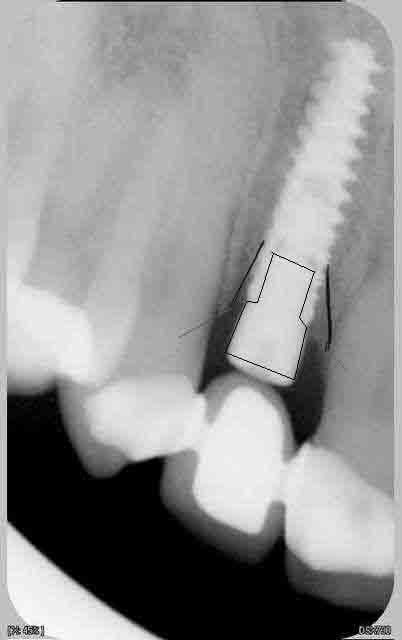

c'est des krestals? Ça n'a pas l'air dramatique sur la radio. Une petite caractérisation qui me parait logique vu la connexion.

On n'a pas les mêmes critères d'exigences. Perdre 4 mm d'os sur 12 soit 1/3.

Attends, sur ces radios t'as 4 mm de perte osseuse? Les vis de cicatrisation sont en place non? Je devine la jonction implant/vis et y a quasiment pas de perte sur tes dernières radio. Enfin je connais pas bien le krestal et la forme de la vis.

Je veux dire, elle est où la perte osseuse sur cette radio? Mais tu as raison, on ne doit pas avoir les même exigences.

La cratérisation est visible beaucoup plus haute: surtout au sondage. L'os que tu vois est en palatin, en vestibulaire, il n'y a plus rien sur cette même longueur.

Sur la molaire, tu ne vois rien aussi.